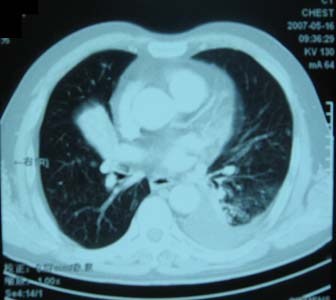

以下是引用zhangzhongshou在2007-5-17 12:08:00的发言:[br]1、右肺中叶不张,建议纤支镜检查。[br]2、左侧胸腔积液,性质待查,建议进一步检查。[br]3、左侧局限性胸膜肥厚。[br][br][本贴已被 zhangzhongshou 于 2007-5-17 12:12:13 修改过]

以下是引用zyx168在2007-5-17 12:44:00的发言:[br]支持[br] 1、右肺中叶不张,建议纤支镜检查。[br] 2、左侧胸腔积液,性质待查,建议进一步检查。[br] 3、左侧局限性胸膜肥厚。 [br]

以下是引用一棵树在2007-5-17 12:11:00的发言:[br]中叶的病变应该谨慎,建议支气管镜检查。